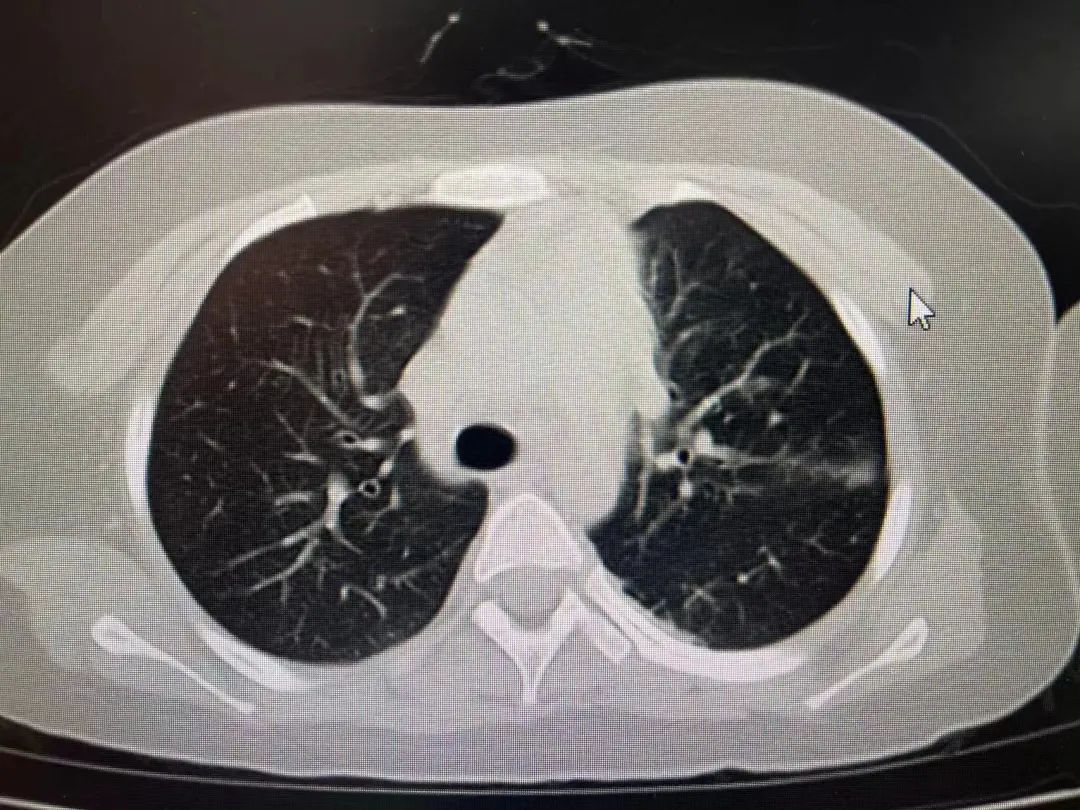

经胸部CT检查,发现患儿双肺都出现了肺不张的情况,超过2/3肺叶实变,再综合血检结果,诊断为重症支原体肺炎,遂住院治疗。在PICU治疗期间,又对症进行了支气管镜灌洗治疗,效果明显。